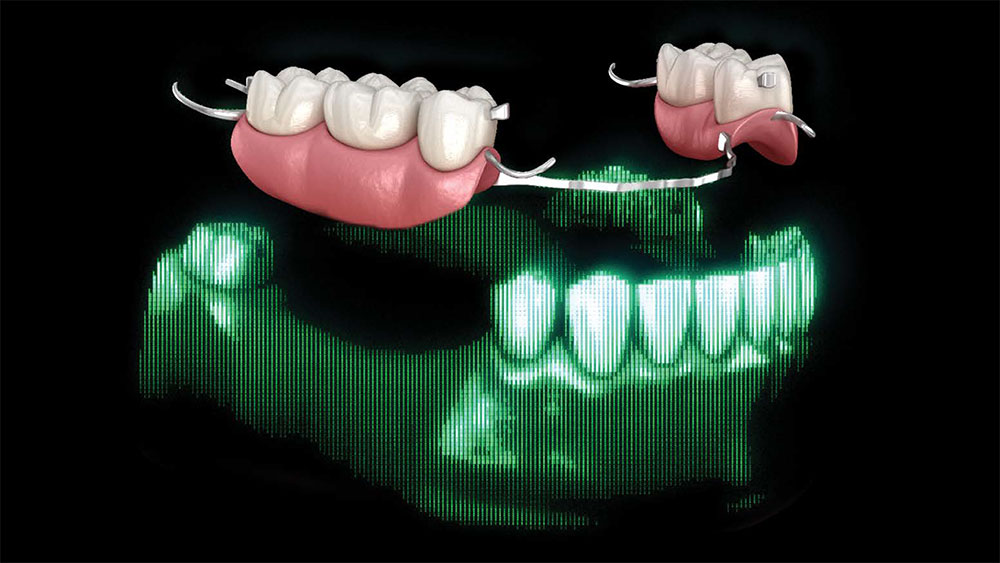

Quality Control at Glidewell

As part of the lab’s quality control process, Glidewell supplies a 3D-printed model and a removable pattern of the partial along with the final crown. This is done in order to check the path of insertion, confirm proper seating and verify engagement with the crown. The photos below show an example of a 3D partial duplicate and model that were supplied with a final crown.

part of the lab’s quality control process